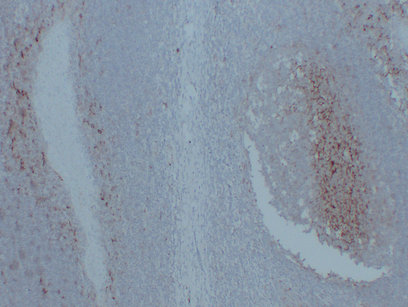

Immunohistochemistry analysis of paraffin-embedded Spleen using CD14 antibody.High-pressure and temperature Sodium Citrate pH 6.0 was used for antigen retrieval.